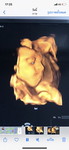

คุณแม่บ้านไหนนอนดึกบ้างค่ะ ปัญหานอนไม่หลับ33week ใครมีประสบการณ์ มีผลอะไรต่อลูกในครรภ์บ้างค่ะ

บ้านนี้ก้อ33wค่ะนอนไม่ค่อยหลับเหมือนกันเเต่ล่ะคืนนอนเกือบตี1เลยค่ะ